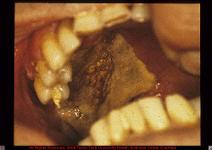

• Mucormycosis